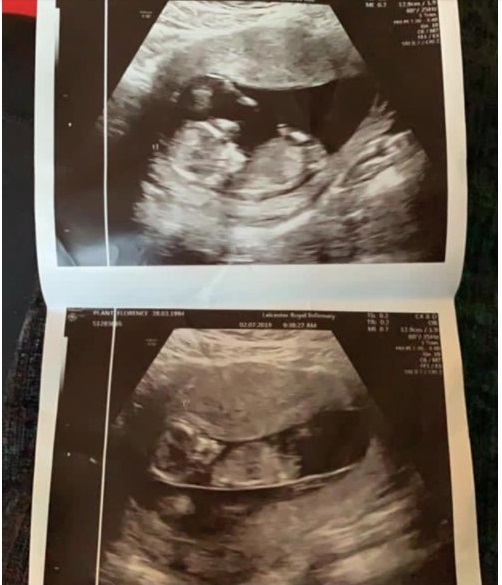

Ngày chị Florence Plant, sinh sống ở Leicester (Anh), nhận được tin thông báo rằng một trong hai đứa con song sinh 25 tuần tuổi thai đã ngừng lại là ngày chị như chết đi một nửa. Nhưng để cứu đứa trẻ còn lại, bác sĩ đã khuyên người mẹ này phải nén đau thương mà chấp nhận chuyện chị sẽ mang bé cho đến khi em bé còn lại chào đời khỏe mạnh. Bác sĩ nói rằng đây là hậu quả của hội chứng truyền máu song thai. Nghĩa là hai em bé đã không nhận được một lượng máu qua nhau thai bằng nhau.

Được biết, quá trình mang thai đôi của chị Florence diễn đều bình thường cho đến tuần thứ 20 của thai kỳ. Lúc đó chị được bác sĩ thông báo rằng hai em bé, Minnie và Hettie, bị mắc phải hội chứng truyền máu song thai. Tình trạng này ảnh hưởng từ 10 đến 15% các cặp song sinh có chung một nhau thai gọi là monochorionic. Nó làm cho các mạch máu trong nhau thai phân tán không đồng đều.

Điều này khiến cho Hettie nhận được nhiều máu hơn trong khi Minnie lại không thể phát triển do nhận ít máu nên bị suy dinh dưỡng. Nhưng vì khi đó thai nhi còn quá nhỏ, không đủ điều kiện để bác sĩ can thiệp bằng cách phẫu thuật nên chỉ có thể theo dõi các em bé thường xuyên. Đến tuần thứ 25, bác sĩ thông báo tin buồn rằng tim của Minnie đã ngừng đập.

Ở tuần 25 của thai kỳ, chị Florence nhận được tin một tim thai đã ngừng đập.